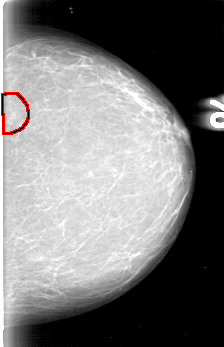

D_4003_1.RIGHT_MLO

D_4003_1.LEFT_CC

LEFT_MLO LINES 5386 PIXELS_PER_LINE 3811 BITS_PER_PIXEL 12 RESOLUTION 43.5 OVERLAY

FILE: D_4003_1.LEFT_MLO.OVERLAY

TOTAL_ABNORMALITIES 1

ABNORMALITY 1

LESION_TYPE MASS SHAPE IRREGULAR MARGINS OBSCURED

ASSESSMENT 0

SUBTLETY 4

PATHOLOGY BENIGN

TOTAL_OUTLINES 1

BOUNDARY